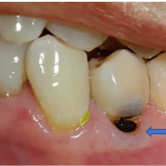

Absceso Periapical Crónico

Un absceso periapical crónico es una infección prolongada en la punta de la raíz del diente que forma una bolsa de pus.

Los pacientes pueden tener dolor leve o no tener síntomas, pero notar una fístula en la encía.

El tratamiento incluye un tratamiento de conducto y, en algunos casos, una cirugía apical. Es crucial tratarlo para evitar la propagación de la infección.